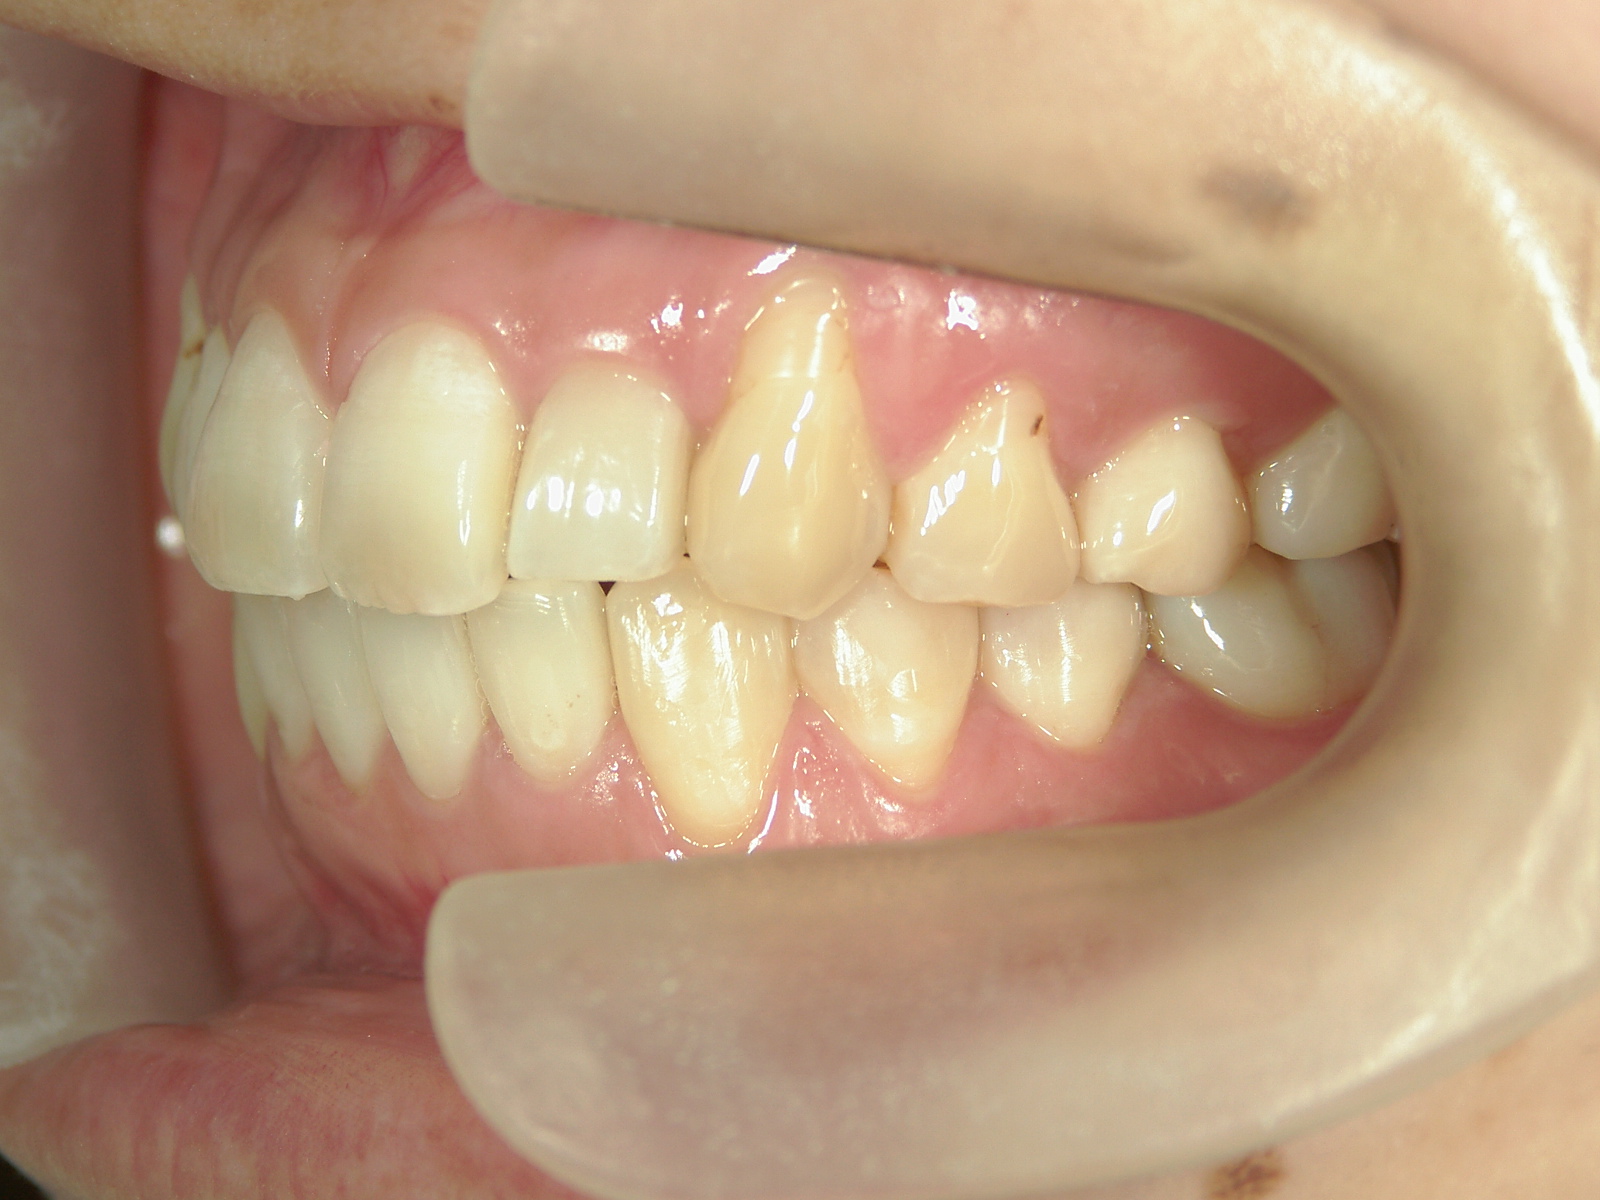

プチワイヤー矯正 症例(53)

| 治療期間 | 9ヶ月 |

カテゴリー : ガタガタ(叢生)